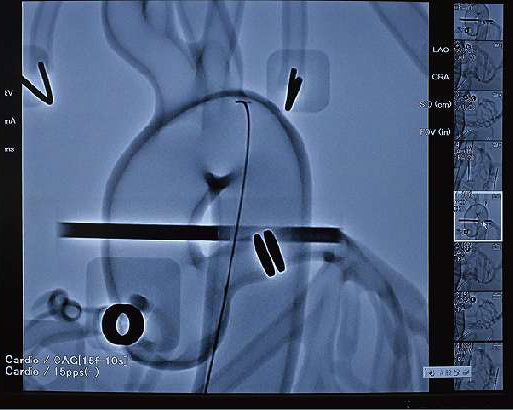

冠動脈手技の全体を目視で立体的に観察できることによって、思いがけないトレーニング効果やカテーテルの総合的評価にもつながります。

- 冠動脈造影検査(CAG)カテーテル操作

- 経皮的冠動脈形成術(PCI)TFI・TRI・TBIアプローチからのガイディングカテーテル・ガイドワイヤー・バルーンカテーテル・ステントなど一連の操作